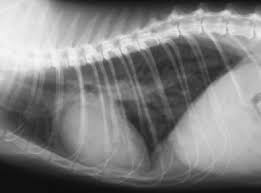

Blässe der Gesichts- und Körperfarbe. Atemnot ist ein typisches Anzeichen wenn Wasser in der Lunge beim Hund zum Problem wird. Bei einigen Erkrankungen treten Lungenödeme Wasser in der Lunge auf und können aufgrund von Atemnot zu starken Beeinträchtigungen führen.

Die Symptome einer Wasseransammlung in der Lunge. Ein Lungenödem ist eine krankhafte Ansammlung von Flüssigkeit in der Lunge. Zu den Symptomen von Wasser in der Lunge gehören.

Typische Symptome eines plötzlich auftretenden Lungenödems sind. Woher kann das kommen.